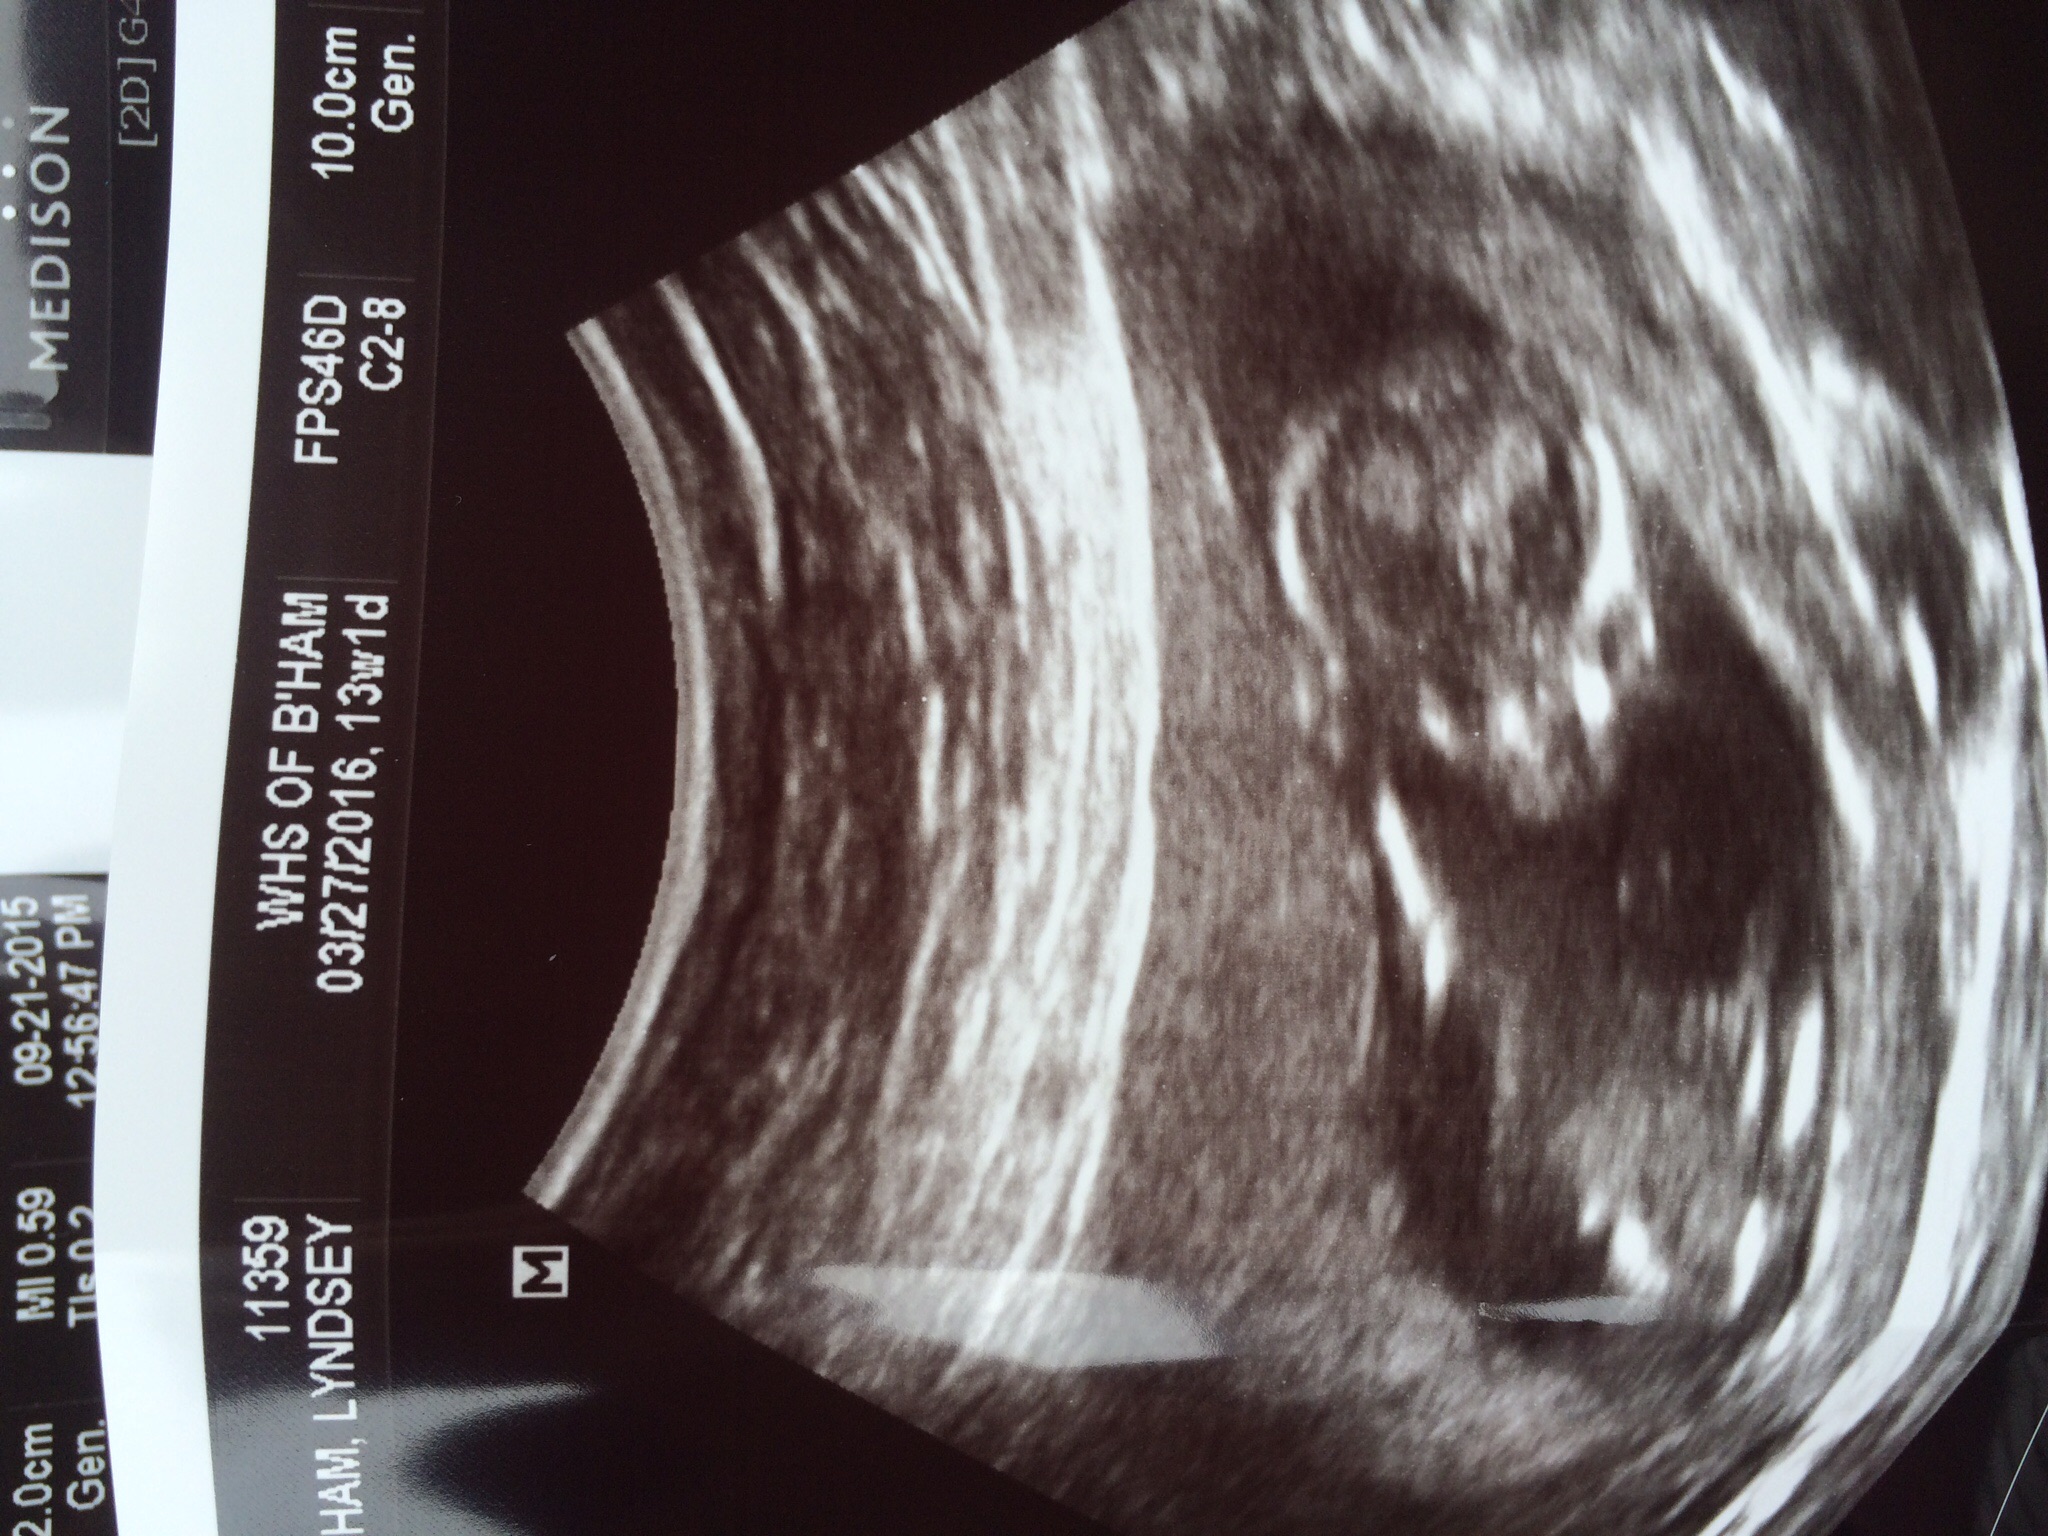

Ok, she is 12 and 4 and placenta in anterior. I know this is a long shot but just for fun! What do yall think?! She has a little girl but she is totally ok with a boy or another girl! Struggled with infertility for years so she is just thankful! Anyway, can you tell anything?!?lolAttachment 27515 looks like a blob to me!haha